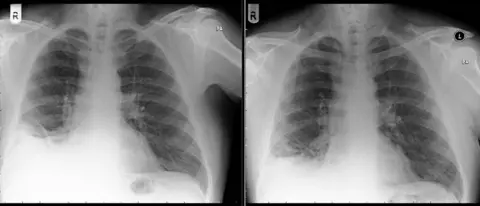

Medics suspected the patient - a long-term smoker - had a tumour when scans showed something on his lung.

However, when they removed the mass they discovered it was the "long lost Playmobil traffic cone" he had received on his seventh birthday.

BMJFour months after the removal of the tiny traffic cone, the patient's cough had almost gone and his symptoms had improved markedly, the report said.